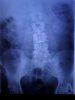

Проблемы со спиной (позвоночником): делимся опытом.